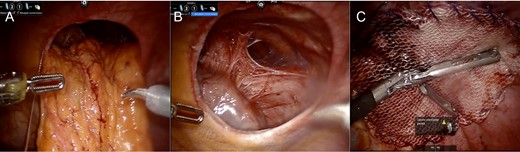

Intraoperative assessment revealed omentum and transverse colon herniating through the left diaphragm defect (Fig. 2A). This was reduced manually without difficulty. The heart was easily seen through the defect (Fig. 2B). The area of the hiatus was evaluated noting a small hiatal hernia. The paraesophageal hernia was repaired in standard fashion with Nissen fundoplication. Attention was turned to the diaphragm defect which was closed using a running 0 permanent V-lock suture. Subsequently, a 12-cm mesh was underlaid and sewn circumferentially using 0 permanent V-lock suture (Fig. 2C). Intraoperative endoscopy demonstrated ease of passage through the GE junction into the stomach.

Intraoperative Images from Case #1. (A) Reduction of omentum and transverse colon through hernia defect. (B) Representative image of defect following reduction of intra-abdominal contents; heart border visible to lower left of defect. (C) Following placement of mesh for repair of diaphragmatic hernia.